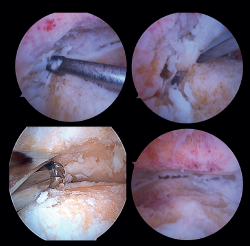

Preparación de superficies articulares (Figura 4)

Figura 4. Preparación de las superficies articulares empleando distintos tipos de instrumental: curetas, escoplos o fresas motorizadas. Imagen final tras la obtener un óptimo lecho subcondral de la articulación tibioastragalina.